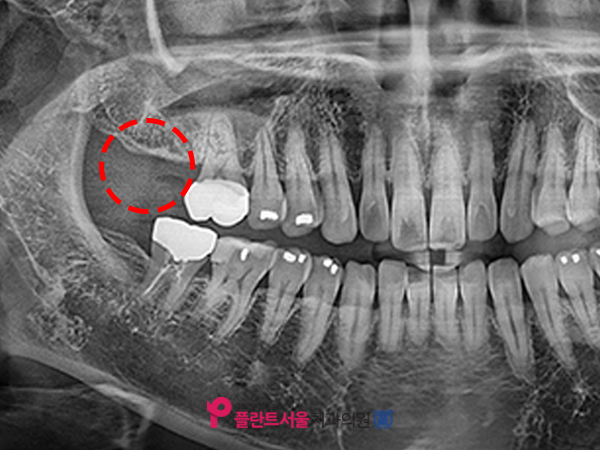

저희 병원에 처음 내원하셨을 때 찍었던 X선 사진입니다. 1년 전 위턱 제2대 어금니(#17)를 발치한 뒤 다시 이곳에 인공 치아를 심기 위해 오포치과 플랜트 서울에 오셨습니다. 환자분의 경우 꽤 오랜 기간 동안 치아가 없는 상태로 지내 왔습니다만. 이와 같이 발치 후에 장기간 그대로 두면 주위 치아가 빈 공간으로 기울어지거나 마주보는 아랫니가 위로 뻗어나와 보철을 심을 공간이 부족할 수 있으며 발치 후에는 가능한 한 빨리 인공치아를 심는 것이 좋습니다.

환자의 경우 다행히 옆에 #16번 치아가 밑에 있는 #47번 치아와 맞물려서 잘 잡고 있어서 부품을 심을 수 있는 충분한 공간이 있었습니다. 본 병원은 보다 정확한 검사를 위해 대학 병원급의 3DCT를 사용하여 환자의 구강 상태를 파악했습니다.